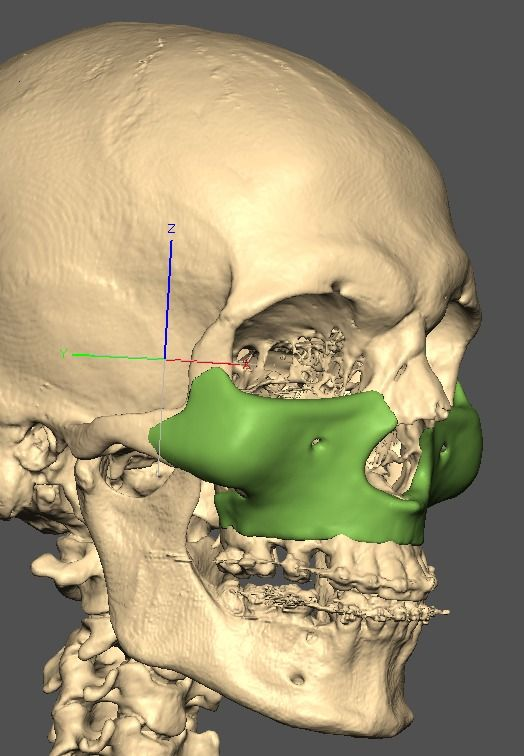

I know a guy who designed this for himself in collaboration with an asian implant company.

Not the final product yet, he is making adjustments as we speak.

Giant and Eppley were the inspiration